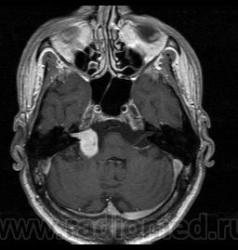

Пациент 35 лет, направлен неврологом из поликлиники с Ds: Рассеянный склероз? У данного пациента в течении года отмечается сильное головокружение и шаткость в походке, пришел на исследование на плечах у родственников. Данное исследование закачено на Dicom-сервер http: //www.radiomed.ru:8080/oviyam/oviyam? (под названием Brain-20101118).

Невринома правого слухового нерва

Если быть точным, VIII нерва;)

Более вероятнее невринома правого слухового нерва.